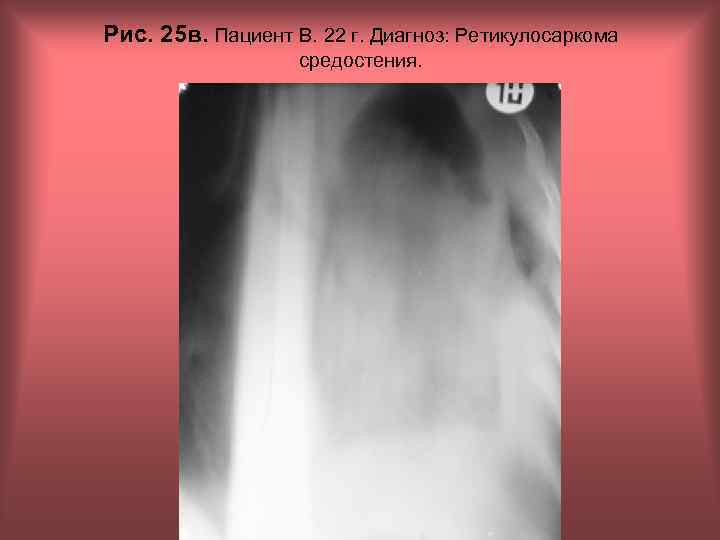

Рис. 25 б. Пациент В. 22 г. Диагноз: Ретикулосаркома средостения. Н. С. Воротынцева, С. С. Гольев Рентгенопульмонология

Рис. 25 в. Пациент В. 22 г. Диагноз: Ретикулосаркома средостения. Н. С. Воротынцева, С. С. Гольев Рентгенопульмонология